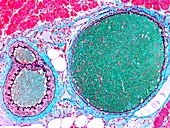

12360983 - Kidney, light micrograph